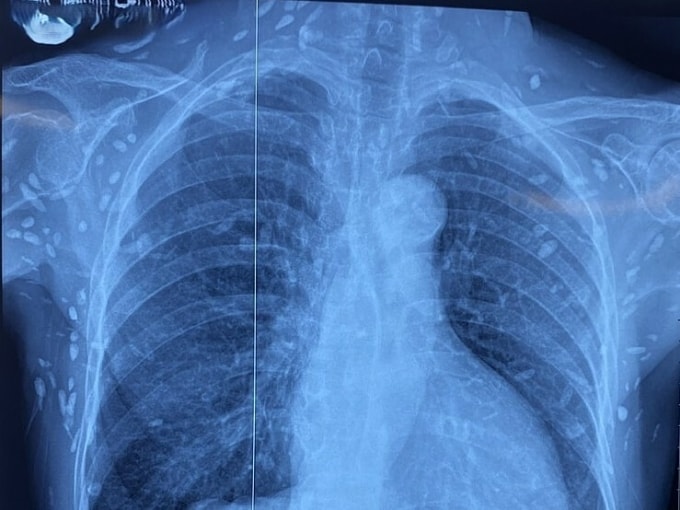

Người phụ nữ 77 tuổi rối loạn ý thức, ảnh chụp CT sọ não và X-quang ngực cho thấy nang sán dây lợn vôi hóa chi chít trong não và cơ thể.

Bà được chuyển lên từ cơ sở y tế tuyến dưới đến Bệnh viện Trung ương Quân đội 108 vì rối loạn ý thức đe dọa suy hô hấp. Hình ảnh cắt lớp vi tính sọ não và X-quang ngực cho thấy rất nhiều nốt cản quang trong nhu mô não và dưới da vùng ngực - bụng. Một vài u cục với kích thước tương ứng có thể sờ thấy dưới da vùng ngực và cánh tay của người bệnh.

Phim chụp cho thấy nhiều nang sán tại thành ngực-bụng và chi trên bệnh nhân. Ảnh: Bệnh viện cung cấp

"Nang sán dây lợn có thể tự thoái hóa hoặc bị vôi hóa, tạo nên hình ảnh cản quang phát hiện được trên phim X-quang như bệnh nhân trên", bác sĩ Thấu nói.